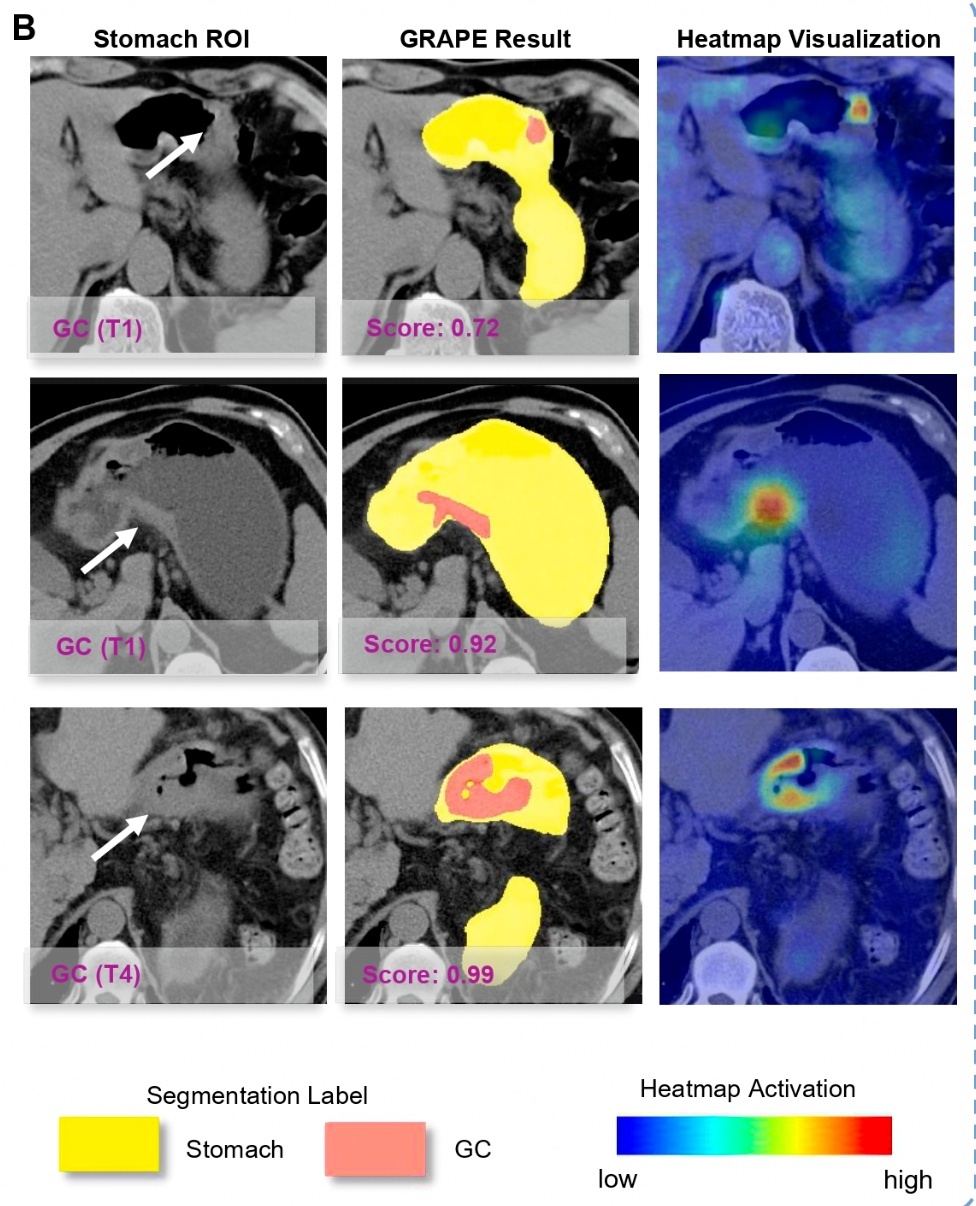

这个定名为DAMO GRAPE的AI模子,明锐性和特异性最终晋升到了85.1% 和 96.8% 。这意味着,诓骗平扫CT筛查胃癌,在表面上成为可能。

随后,团队聚首世界20 个中心,开展了秘密近10万东谈主的临床盘考,并在浙江平阳、奉化的两家地区病院部署了模拟契机性筛查磨砺,检出率辞别达到24.5%与17.7%。

▲AI能识别各阶段胃癌